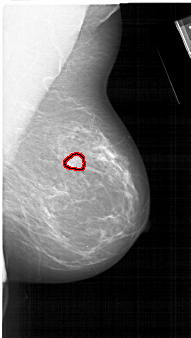

FILE: A_1134_1.RIGHT_MLO.OVERLAY

TOTAL_ABNORMALITIES 1

ABNORMALITY 1

LESION_TYPE MASS SHAPE IRREGULAR MARGINS SPICULATED

ASSESSMENT 4

SUBTLETY 4

PATHOLOGY MALIGNANT

TOTAL_OUTLINES 1

BOUNDARY